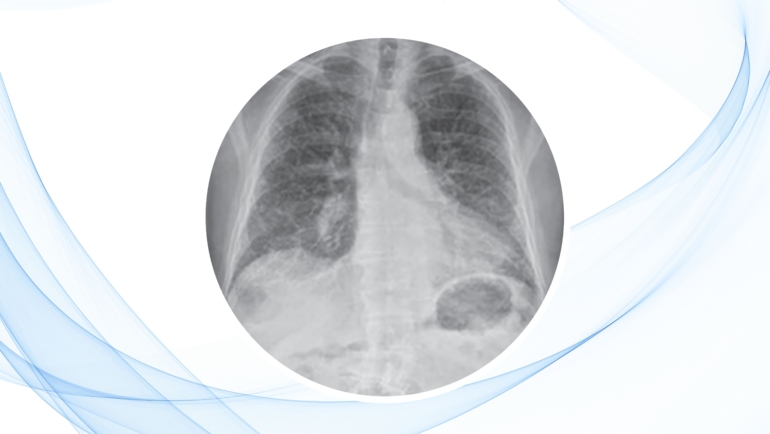

En este capítulo, los autores presentan un enfoque sistemático para el diagnóstico y manejo de las neumonías, incluyendo herramientas prácticas como las escalas CURB-65 y PORT, fundamentales para evaluar la gravedad de la neumonía y tomar decisiones clínicas acertadas.

La escala CURB-65 es una herramienta clínica que permite clasificar la gravedad de la neumonía y orientar la necesidad de hospitalización. Se basa en cinco criterios clínicos:

Esta escala se presenta en el Diagrama de flujo 7.1 del capítulo, y se complementa con el acrónimo ADMIT NOW, que resume otras indicaciones para ingreso hospitalario, como inmunosupresión, afectación multilateral, o leucocitos extremos.

Indicaciones clínicas para hospitalización en neumonía

- Afectación de dos o más lóbulos pulmonares